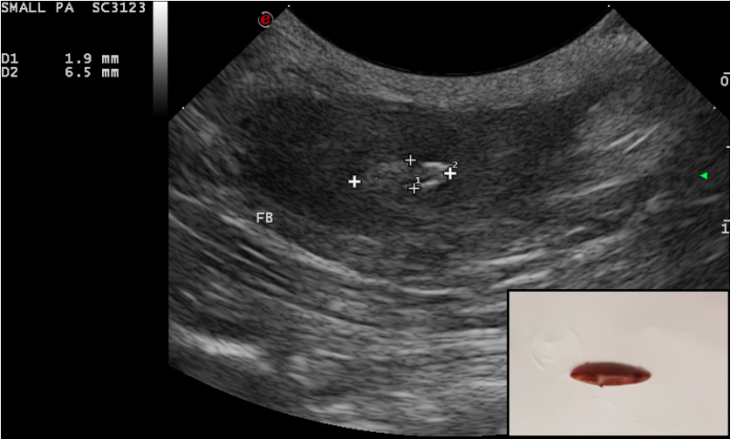

The use of ultrasound for the detection of such foreign bodies is well known and their ultrasonographic features have been widely discussed. Grass awns ‘appear as linear spindle-shaped hyperechoic structures of variable length, with two or three parallel reflecting interfaces corresponding to the seeds and seed covers. Often an anechoic halo due to the accumulation of fluid is present around the foreign body, which sometimes improves interface visualisation’.

Four dogs referred for recurrent abscess in the lumbar region have been seen at the hospital between October 2018 to January 2019. A migrating vegetal foreign body was identified in each dog with the use of ultrasonography. All retrieval procedures were performed in the sonography suite with the patient under general anaesthesia. The region of interest was aseptically prepared and a small stab incision with a #11 scalpel was performed approx. 2 cm cranial to the foreign body, with the plant awn imaged in sagittal section. A Hartmann forceps was inserted through the skin incision and directed toward the tip of the foreign body under ultrasonographic guidance. The forceps were opened and the foreign body grasped and withdrawn. The shape of the foreign body was compared with the sonographic images and the site of the abscess was re-scanned to determine potential residual foreign bodies or fragments. In all dogs, the abscess was flushed with saline and oral antibiotic therapy was administered for 7–10 days. The duration of the procedure ranged from 20 to 40 minutes. Suture of the skin incision was not necessary.